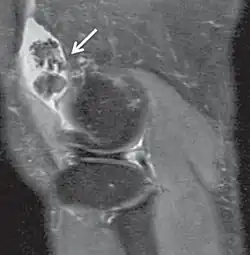

| Proton density weighted | PD | Long TR (to reduce T1) and short TE (to minimize T2).[7] | Joint disease and injury.[8]

T2* | Spoiled gradient recalled echo (GRE) with a long echo time and small flip angle[11] | Low signal from hemosiderin deposits (pictured) and hemorrhages.[11] |

| Inversion recovery | Short tau inversion recovery | STIR | Fat suppression by setting an inversion time where the signal of fat is zero.[13] | High signal in edema, such as in more severe stress fracture.[14] Shin splints pictured: |